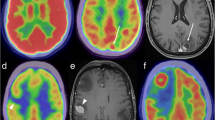

A recent study, in a small group of patients with neurodegenerative and vascular disorders, investigated the performance of hybrid PET/MRI, using 18F-FDG as the PET tracer. A superior specificity of MRI for vascular lesions was found. Conversely, a superior specificity of PET metabolic patterns was observed with regard to accurate diagnosis of Lewy body dementia and frontotemporal dementia (validated by clinical diagnosis at follow-up) [16]. Figure 2 shows a representative case of frontotemporal dementia with concordant PET and MRI data. This finding is consistent with previous literature data [35, 36].

Imaging of neurodegeneration by PET/MRI. 18F-FDG PET/MRI study in a patient with clinical suspicion of degenerative dementia: the images show concordant information on both modalities, i.e. diffuse atrophy on MRI and significant hypometabolism in frontal regions, typical of frontotemporal dementia (study acquired on the Biograph mMR whole-body, Technische Universitat Munchen, Munich, Germany)

To date, only a few PET/MRI studies on epilepsy have been reported [16, 27]. One report on six cases studied by sequential PET/MRI hybrid imaging showed that fusion of morphological and functional information allowed the identification of subtle metabolic alterations which could easily have been missed when interpreting the 18F-FDG images alone [16]. Figure 3 shows images of a PET/MRI study in a pediatric case. Another study demonstrated the feasibility of simultaneous 11C-flumazenil PET and MPRAGE MRI acquisition in one patient with right temporal lobe epilepsy [27].

Imaging epilepsy by PET/MRI. 18F-FDG PET/MRI study showing concordant information on the two modalities, i.e. right temporal hypometabolism associated with hippocampal sclerosis and amygdalo-hippocampal dysplasia in a pediatric patient (study acquired on a Philips Ingenuity TF PET/MRI, Geneva University Hospitals, Geneva, Switzerland)